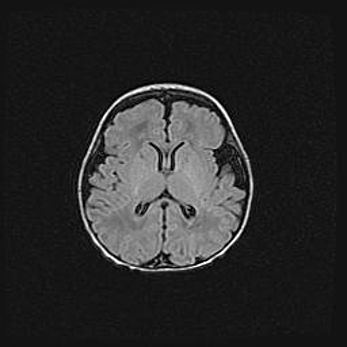

Наружная гидроцефалия с возможной атрофией височных областей.

Возраст: 28 дней

Вес: 3670 г

Пол: мужской

Окружность головы: 38 см

Срок гестации: 40 недель

Гидроцефалия головного мозга у новорожденных – это заболевание, которое характеризуется скоплением избыточного количества спинномозговой жидкости в желудочковой системе головного мозга в результате затруднения её перемещения от места выработки к месту поглощения в кровеносную систему или вследствие нарушения абсорбции. При открытой наружной форме гидроцефалии у новорожденных расширяются и переполняются субарахноидные пространства.

При нормотензивных  формах,  которые,  как  правило,  являются  следствием  перенесенных ишемических  повреждений  паренхимы  мозга,  возможно  сочетание микроцефалии  с нормотензивной гидроцефалией. В основе данных изменений лежит атрофия больших полушарий с преимущественной  локализацией  в  лобно-височных  областях.